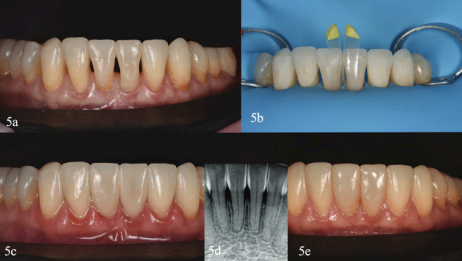

Minimally Invasive Treatment of Open Gingival Embrasures (Black Triangles)

This article explores how black triangles—caused by open gingival embrasures—can be managed conservatively using direct composite restorations with the Bioclear Method. These spaces are often a cosmetic concern for patients, particularly post-orthodontics or in periodontally compromised cases.

Technique Summary: Bioclear Black Triangle Protocol